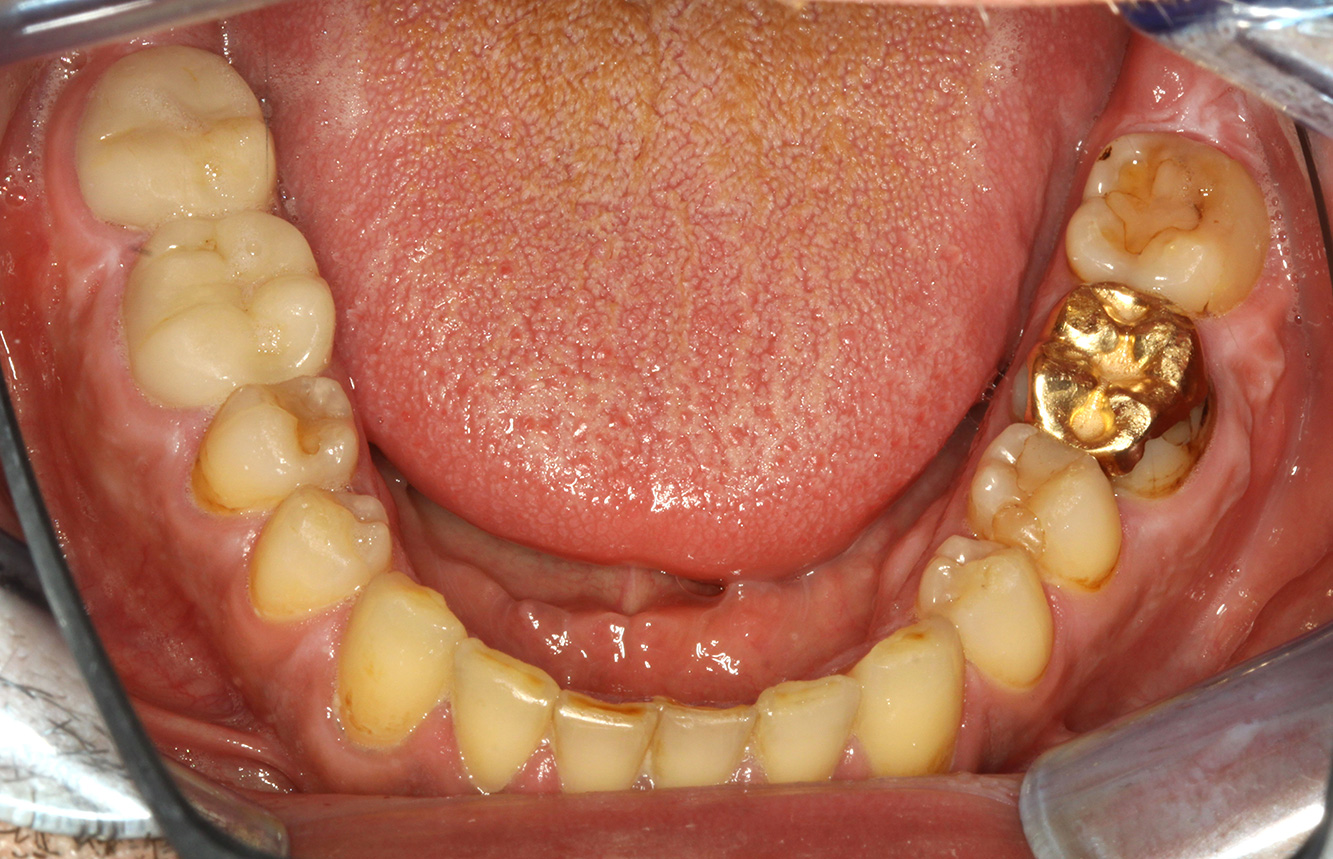

In the medical history, the 55-year-old patient states that he has no systemic disease and is not taking any medication. The patient’s lifestyle is similarly unremarkable. The patient has a few tooth restorations and two implants (2nd and 4th quadrants). On the basis of current findings, gingivitis is identified in an otherwise stable periodontal condition on the reduced periodontium (stage III, grade A). more

The healthy patient with pre-existing periodontal disease & peri-implantitis

The 68-year-old patient has no general health conditions and is not taking any medication that may be relevant to her oral health, and her lifestyle does not pose any particular risk. The patient has two dental implants (3rd quadrant, for five years) and a previous case of periodontal disease (stage IV, grade B periodontitis) with tooth loss. Currently the periodontal conditions are stable. However, periodontitis significantly increases the biological complications of implantations and there is a risk of implant loss (21). Four recommendations can be determined for the prophylaxis session. more